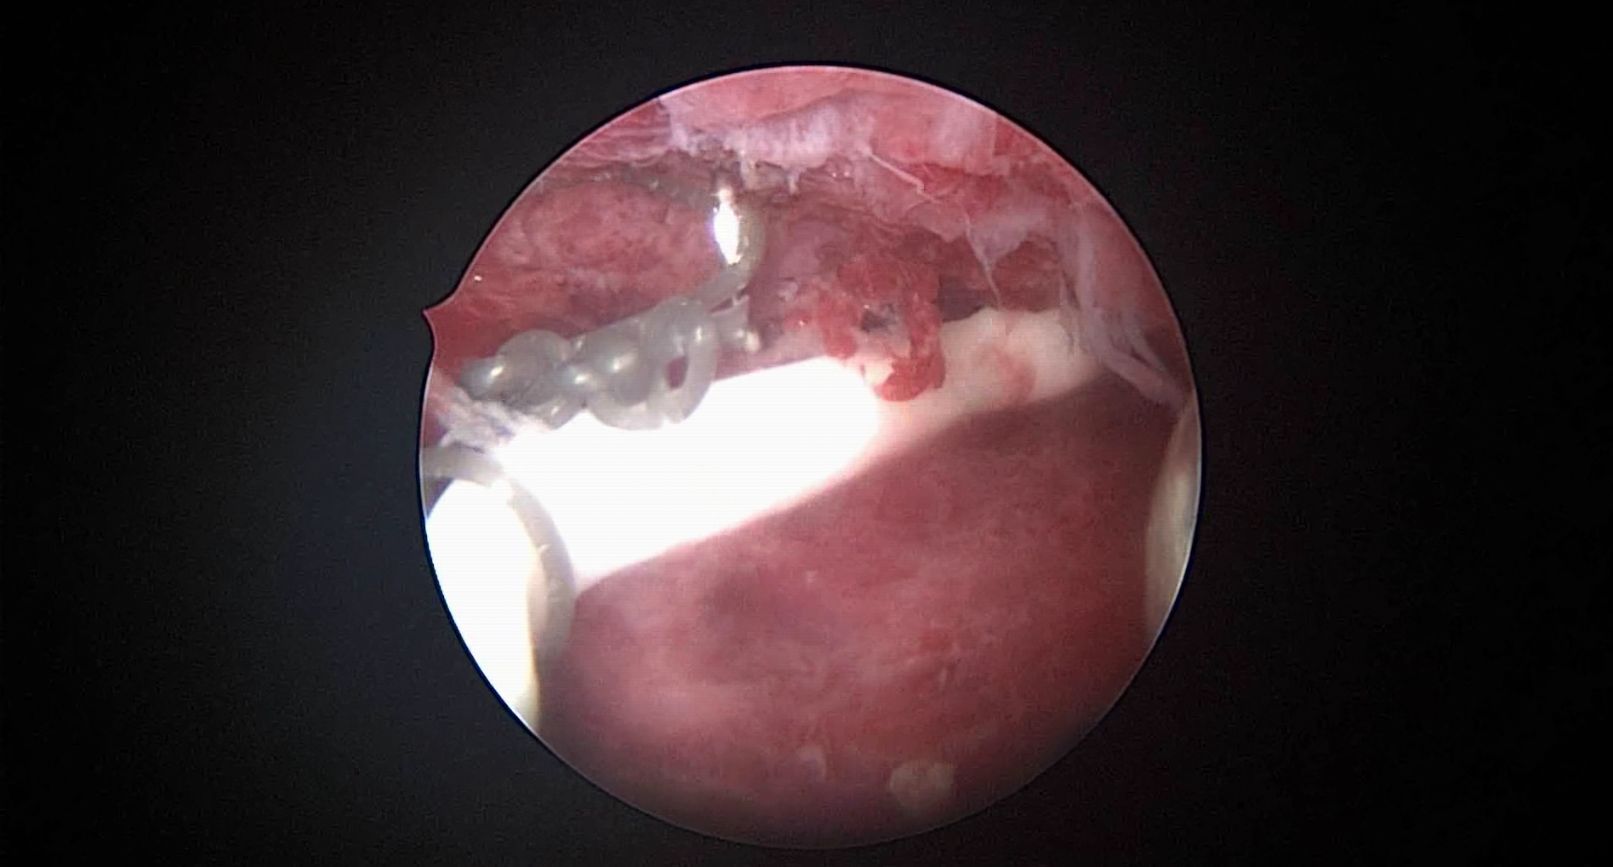

患者41岁,G4P2,顺产2次。因异常子宫出血于2023年12月在外院行宫腔镜检查,取内膜病检为增生晚期及分泌早期宫内膜组织,另见宫内膜息肉,术后药物治疗效果不佳,月经周期不规律。本次阴道不规则流血10+天,量多就诊。宫腔镜下尝试线结扣宫底锚定曼月乐,将结推人宫底肌层很困难,最后采用不锈钢挂钩固定。用曼月乐尾丝连接环与不锈钢挂钩,将挂钩插入宫底肌层,异物钳原位固定曼月乐,退出宫腔镜,结束手术。术后患者未回院复查节育环位置。